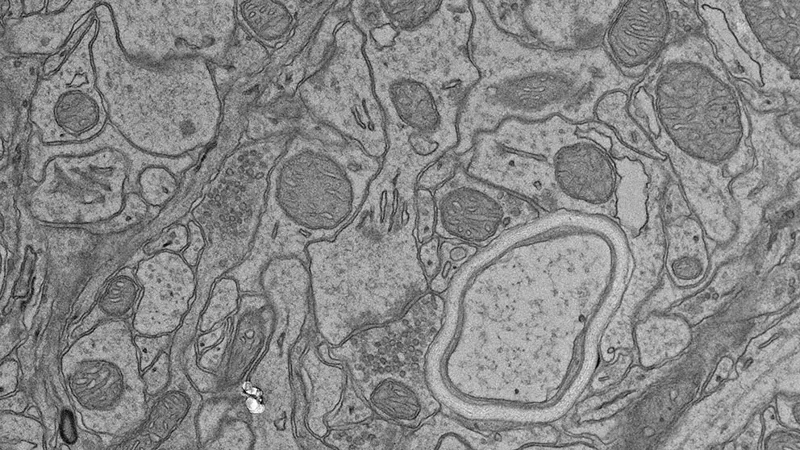

Histopathology Sciences (HPS) provides cutting-edge services enabling analysis of a wide range of anatomical, biochemical, protein, cell, and cell surface characteristics in tissue, blood, urine, and cerebrospinal fluid from various mouse models. The results are critical for numerous and varied phenotyping studies, monitoring disease progression, and determining response to drug treatments or effects of environmental factors. For example, investigators using mouse models of retinopathy rely on the work of HPS to identify lesions in the eye using both Histology and Electron Microscopy Services. The Histology and Clinical Chemistry Services partner with the JAX Diagnostic Program team and Clinical Pathologists to safeguard the health of JAX mouse colonies through the JAX colony monitoring program. The Histology and Electron Microscopy Services can also process fixed human tissue or cultured cell samples, patient-derived xenografts, and non-mammalian vertebrate samples. Our managers and experienced staff are available for consultation. Working together, they provide experimental design support and establish workflows to ensure that investigators can obtain the clearest results for their research.